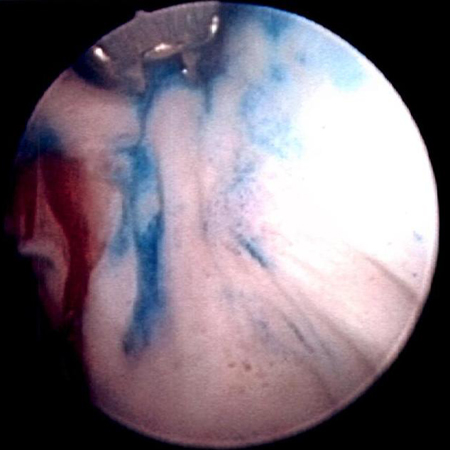

[Figure caption and citation for the preceding image starts]: Carcinoma urotelial papilar não invasivo (Ta) de baixo grau; observe o tumor satélite adjacente, ilustrando o efeito de campoDo acervo de Donald Lamm, MD, FACS [Citation ends].

[Figure caption and citation for the preceding image starts]: Tumor tingido com azul de metileno no colo vesical direito. A coloração com azul de metileno a 0.2% (ou o uso de cistoscopia por fluorescência azul clara com hexaminolevulinato) pode ajudar a identificar tumores não observados de outra formaDo acervo de Donald Lamm, MD, FACS [Citation ends].